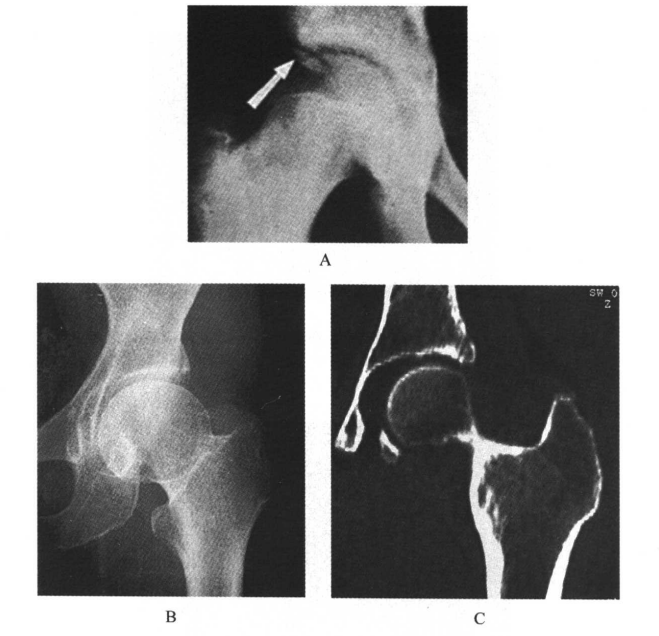

7.在正位片上,14~18岁时髋臼外上缘可能出现多余的化骨核,呈三角形或卵圆形,有时可分裂成3~4个小块,称髋臼缘骨(图7)。

图7 髋臼缘骨A.X线平片,右上髋臼缘骨;B.X线平片,左上髋臼缘不规整,有一裂隙,疑为骨折;C.与B同一病例的CT-MPR,左上髋臼缘骨(注意游离骨块周边有皮质骨白线围绕)